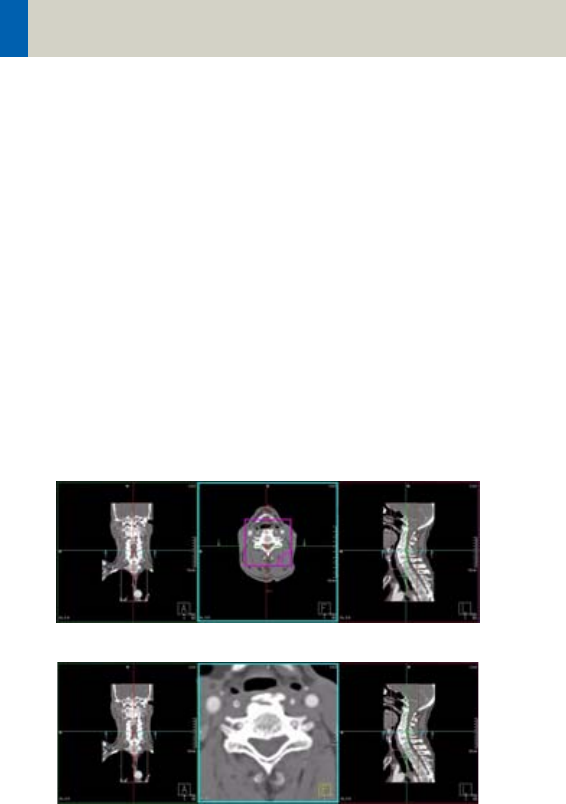

- C-Spine 298

- C-SpineVol 300

- SpineRoutine 302

- SpineThinSlice 304

- SpineVol 305

Contents

11

- SpineSeq 308